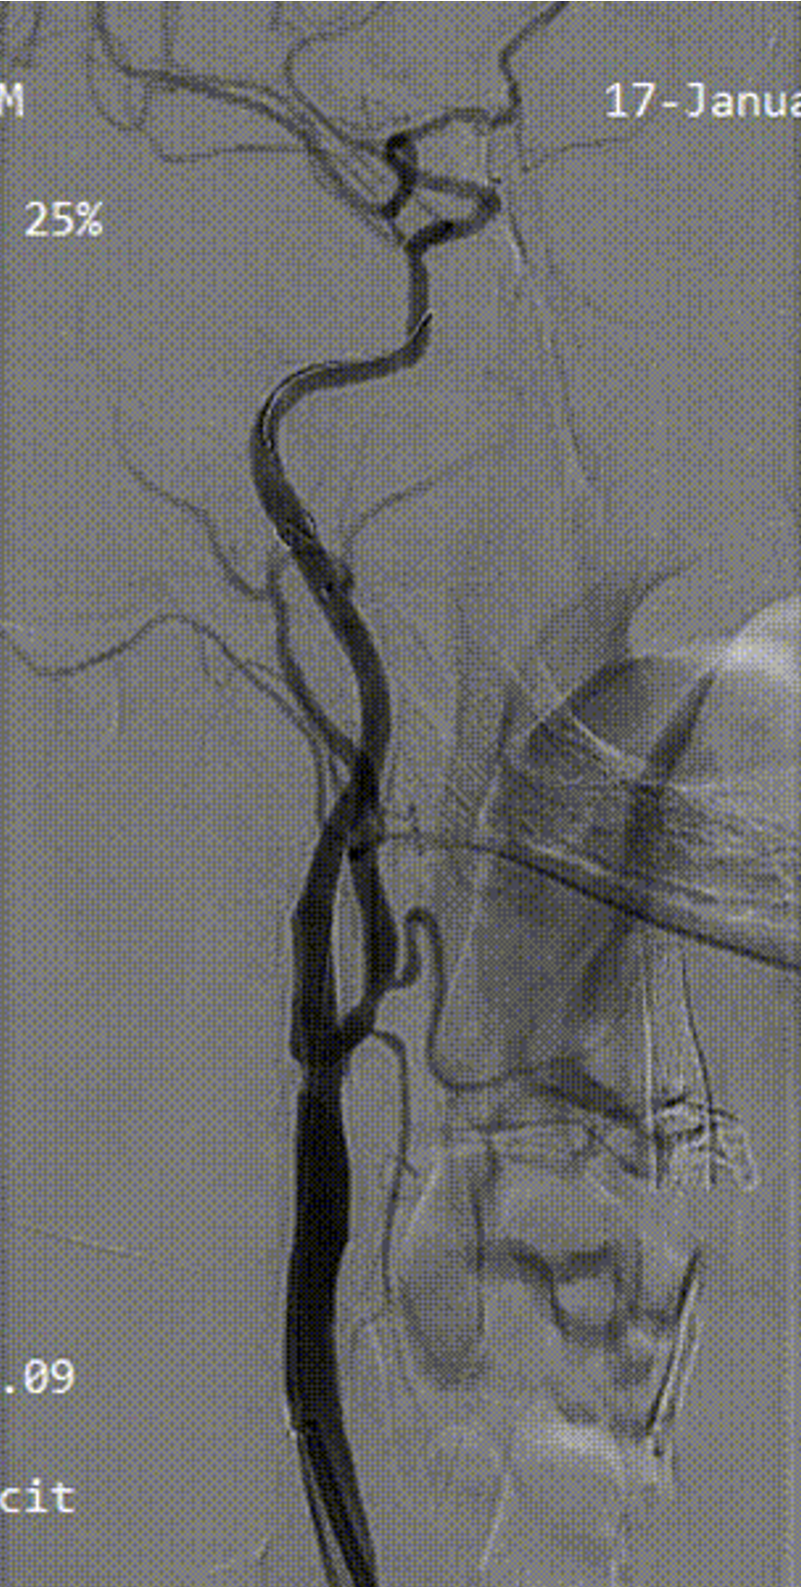

病例3:62岁男性,发作性胸痛9个月,外院行PCI后仍有症状,拟冠脉搭桥前发现双侧颈动脉狭窄,行双侧CAS,先右后左,3个月后行左侧CAS,术后复查彩超显示支架通畅,1个月后行冠脉搭桥手术。

右侧术前

右侧术后

左侧术前

左侧术后